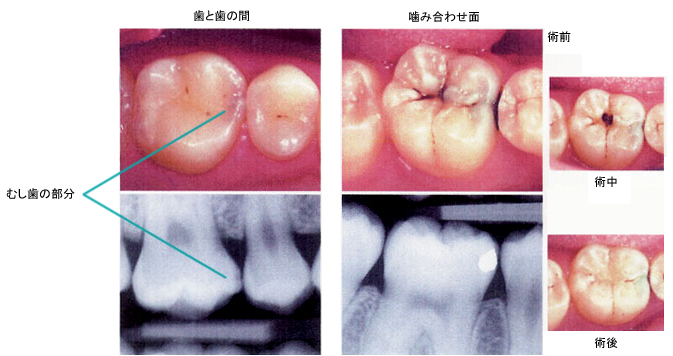

CASE 02 比較的大きいむし歯

【病態】

【治療(過程)】